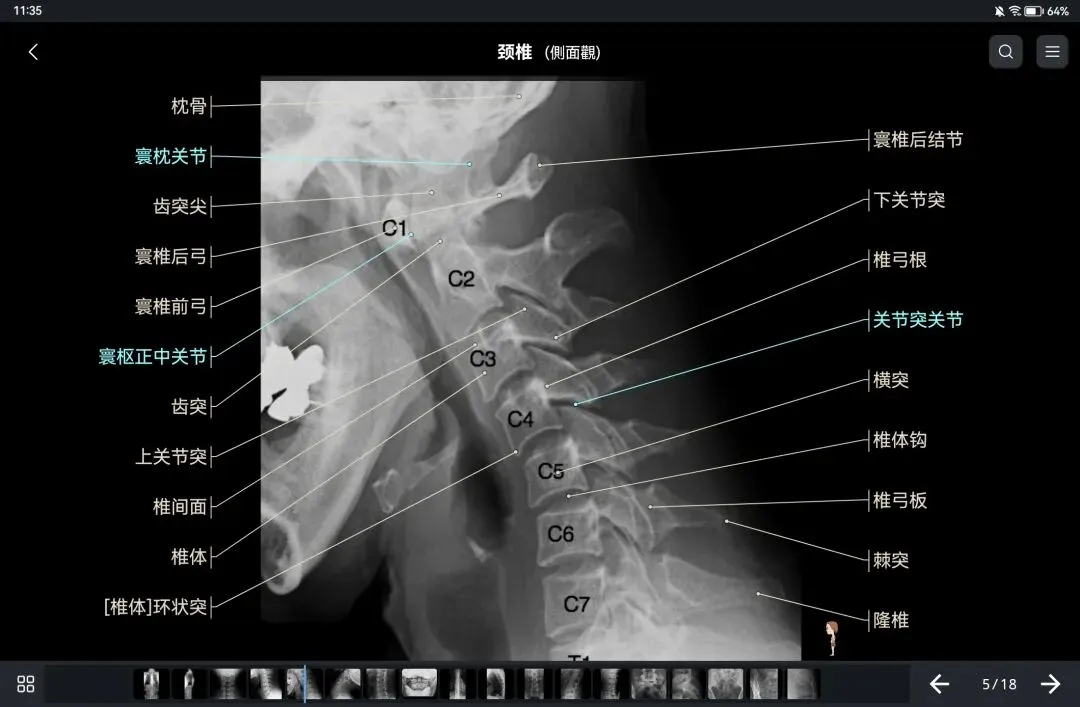

覆盖了X光、CT、MRI、断层大体解剖、核医学、介入造影、医学插图等多个模块,覆盖全身各个系统的影像解剖(正常解剖结构,无病例),其中的解剖结构高达87万个,结构标注超精细,超高清图像,历时两年研发设计完成✅。